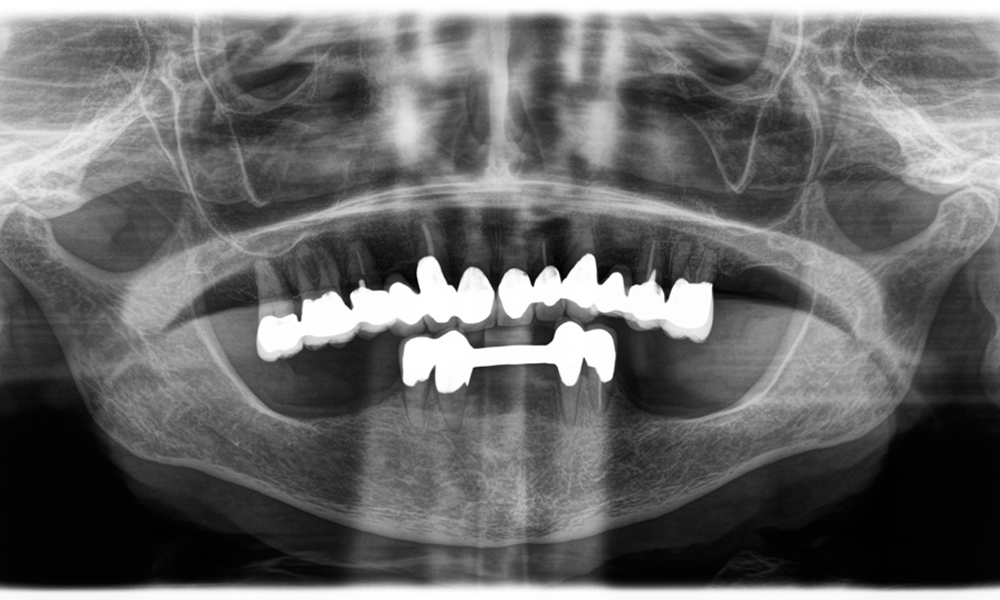

El Dr. Wolfgang Tautschnig, un experimentado odontólogo de Salzburgo, ha utilizado y evaluado Synea Power Edition durante varios meses en su consulta en diferentes escenarios clínicos. Entre ellos, para la extracción de coronas de zirconio y el mecanizado de aleaciones comunes. En un caso concreto, una paciente de 81 años acudió porque quería mejorar el aspecto de sus coronas de metal-cerámica de hacía 40 años. Las coronas existentes ya no satisfacían las exigencias estéticas de la paciente.

El reto consistía en extraer doce coronas bloqueadas con aleación común sin dañar los raigones subyacentes. Se utilizó el contra-ángulo para realizar incisiones precisas en las capas de cerámica y separar las estructuras metálicas con una fresa de metal duro, con el fin de extraer las coronas con un traumatismo mínimo. En solo 30 minutos se retiraron las coronas antiguas y se pudo preparar el nuevo trabajo, compuesto por zirconio completo en la zona posterior y coronas con recubrimiento en la zona anterior. El resultado fue una reconstrucción completa, satisfactoria tanto desde el punto de vista funcional como estético (véase la fig. 1).